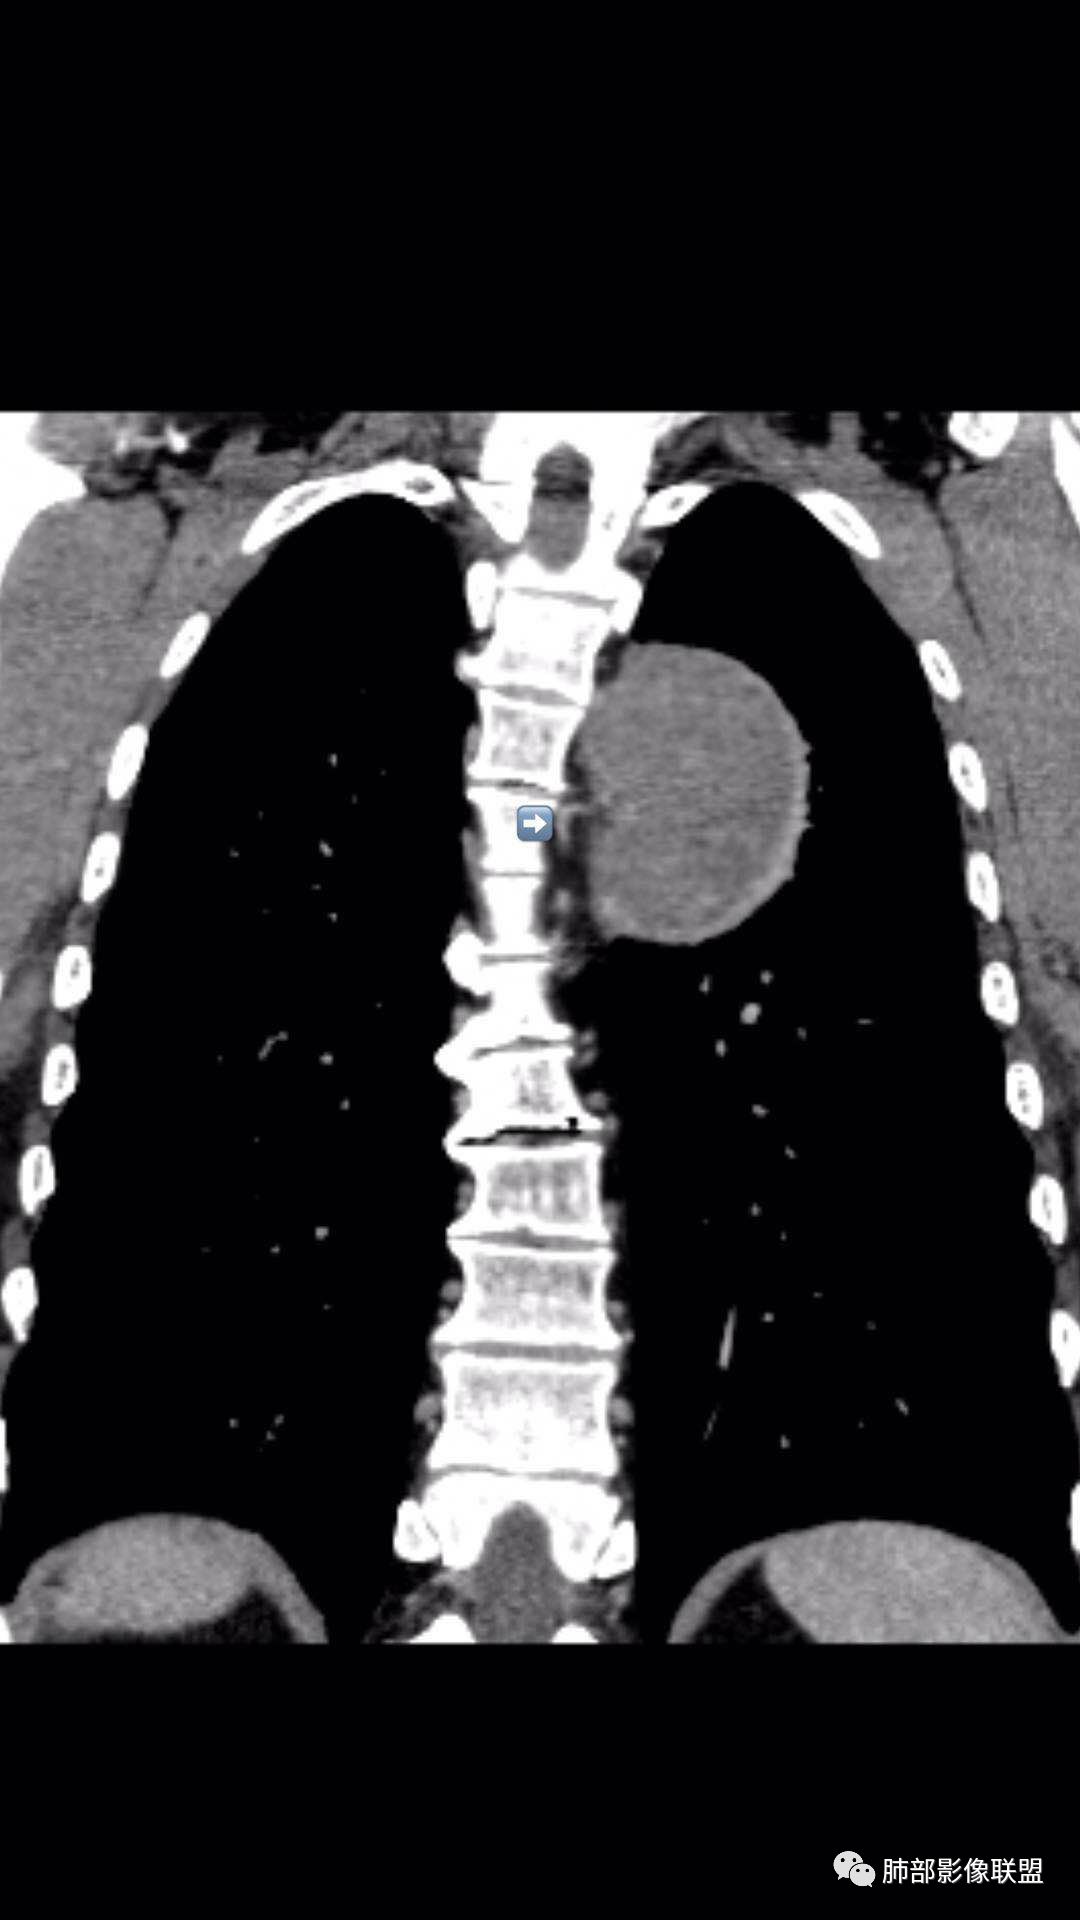

是这样,如果是胸膜来源的SFT,在脊柱和病灶之间应该会有脂肪层,但是这个脂肪层没有,所以不太考虑SFT,支持神经鞘瘤。而且供血看不清,似乎是这个。

阚:内侧有脂肪是不是说明是掀起?

不要说根据椎间孔的位置,就是附近的脂肪推移都可以判断其方向

南边:

问题是大病灶,而且椎间孔没累及

我们该如何判断其来源于胸膜还是纵隔

我们其实判断定位:胸膜的变化?推移、增厚,合并胸水更好,看起与胸水的位置关系利于判断

病灶的主题区域、前方没有,就更支持胸膜外或壁层胸膜的,将水外推

徐超:胸水在胸膜腔,图像太厚了首先肺外确定的,近脊柱如果是强化的壁层胸膜,与肿块间隙还有疑微积液,冠状位有一层胸膜外脂肪间隙存在清楚,都提示胸膜来源,主要是确定下内侧结构是否是壁层胸膜,如果是迎刃而解,如果胸膜外,无论哪一层壁层胸膜都是向肺的地方彭隆的。我也支持脏层可能大

术后病理后纵隔神经鞘瘤